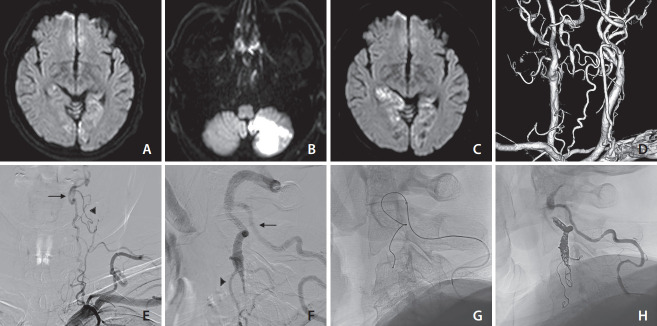

Vertebral artery stump syndrome (VASS) is a rare condition that can cause posterior circulation ischemic stroke due to occlusion of the ipsilateral vertebral artery (VA) orifice, resulting in blood flow stagnation and embolus formation. Although there is no established treatment for this condition, we observed 3 cases of VASS out of 326 acute ischemic stroke cases at a single institution from April 2021 to October 2022. Despite the best possible antithrombotic treatment, all 3 patients had recurrent ischemic strokes. One patient underwent drug-eluting stenting of the VA orifice to relieve occlusive flow. The other 2 patients received coil embolization, which resulted in the disappearance of their culprit collateral flow. None of the patients had recurrent ischemic strokes after endovascular intervention. Based on our observations, stenting and coil embolization are effective methods for preventing future recurrences of VASS.

Abstract Image